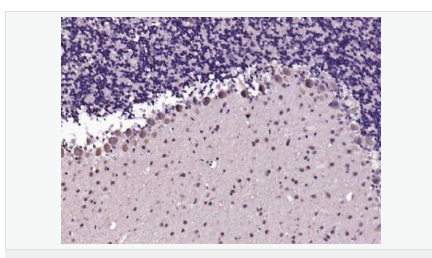

| 產(chǎn)品應(yīng)用 | WB=1:500-2000 IHC-P=1:100-500 IHC-F=1:100-500 Flow-Cyt=1μg/Test ICC=1:100-500 IF=1:100-500 (石蠟切片需做抗原修復(fù)) not yet tested in other applications. optimal dilutions/concentrations should be determined by the end user. |

| 產(chǎn)品介紹 | This gene encodes a member of the membrane-associated guanylate kinase (MAGUK) family. It heteromultimerizes with another MAGUK protein, DLG2, and is recruited into NMDA receptor and potassium channel clusters. These two MAGUK proteins may interact at postsynaptic sites to form a multimeric scaffold for the clustering of receptors, ion channels, and associated signaling proteins. Multiple transcript variants encoding different isoforms have been found for this gene. [provided by RefSeq, Jul 2008] Function: Interacts with the cytoplasmic tail of NMDA receptor subunits and shaker-type potassium channels. Required for synaptic plasticity associated with NMDA receptor signaling. Overexpression or depletion of DLG4 changes the ratio of excitatory to inhibitory synapses in hippocampal neurons. May reduce the amplitude of ACCN3 acid-evoked currents by retaining the channel intracellularly. May regulate the intracellular trafficking of ADR1B. Subunit: Interacts with ANKS1B, KLHL17 and PRR7. Interacts through its PDZ domains with NETO1. Interacts through its first two PDZ domains with GRIN2A, GRIN2B, GRIN2C, GRIN2D, ACCN3, certain splice forms of GRIN1, KCND2, CXADR and SYNGAP1. Interacts through its second PDZ domain with the PDZ domain of NOS1 or the C-terminus of CAPON. May interact with HTR2A. Interacts through its guanylate kinase-like domain with DLGAP1/GKAP, DLGAP2, DLGAP3, DLGAP4, MAP1A and BEGAIN. Interacts through its third PDZ domain with CRIPT (By similarity). Interacts through its first two PDZ domains with KCNA1, KCNA2, KCNA3, KCNA4 and ERBB4. Interacts through its first PDZ domain with GRIK2, KCNA4 and CRIPT. Interacts through its third PDZ domain with NLGN1, and probably with NLGN2 and NLGN3. Interacts through its guanylate kinase-like domain with KIF13B. Isoform 2 interacts through an L27 domain with HGS/HRS and the first L27 domain of CASK. Interacts with LRFN1, LRFN2 and LRFN4. Interacts with ANO2, ADAM22 and LGI1. Interacts with FRMPD4 (via C-terminus). Interacts (via PDZ1 and PDZ2 domains) with LRRC4; LRRC4B and SEMA4C. Interacts (via guanylate kinase-like domain) with SIPA1L1. Subcellular Location: Cell membrane; Peripheral membrane protein. Cell junction, synapse, postsynaptic cell membrane, postsynaptic density. Cell junction, synapse. Cell junction, synapse, synaptosome. Note=High levels in postsynaptic density of neurons in the forebrain. Also in presynaptic region of inhibitory synapses formed by cerebellar basket cells on axon hillocks of Purkinje cells. Tissue Specificity: Brain. Post-translational modifications: Palmitoylation of isoform 1 is required for targeting to postsynaptic density. Similarity: Belongs to the MAGUK family. Contains 1 guanylate kinase-like domain. Contains 3 PDZ (DHR) domains. Contains 1 SH3 domain. SWISS: P78352 Gene ID: 1742 Database links: Entrez Gene: 1742 Human Entrez Gene: 13385 Mouse Omim: 602887 Human SwissProt: P78352 Human SwissProt: Q62108 Mouse Unigene: 463928 Human Unigene: 27256 Mouse Unigene: 9765 Rat Important Note: This product as supplied is intended for research use only, not for use in human, therapeutic or diagnostic applications. 該蛋白質(zhì)PSD95能夠幫助建立神經(jīng)突觸的架構(gòu),并且促成突觸其他部分的成熟,例如加強(qiáng)目標(biāo)細(xì)胞上的glutamate受體的聚集、增加樹突棘(dendritic spines)的數(shù)量和大小以及增加神經(jīng)傳導(dǎo)物質(zhì)glutamate (谷氨酸鹽)釋放的量。這種蛋白質(zhì)與阿滋海默癥有關(guān)。 |